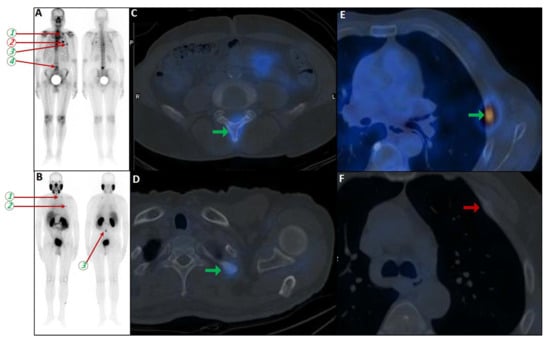

Background/Objectives: Extramedullary involvement in multiple myeloma represents an aggressive disease phenotype, associated with reduced survival and an unfavorable prognosis. Thoracic manifestations are rare and remain poorly characterized in the literature. Methods: We conducted a retrospective, single-center study at the Fundeni Clinical Institute, including patients diagnosed with multiple myeloma between February 2010 and February 2025. The study cohort consisted of 34 patients with infiltration of the pulmonary parenchyma, pleura, or the presence of myelomatous pleural effusion. Diagnosis was confirmed using a combination of imaging modalities (computed tomography or magnetic resonance imaging), cytological examination, immunophenotyping, and histopathological confirmation whenever feasible. Results: Out of a total of 2012 patients with multiple myeloma, the incidence of pleuro-pulmonary extramedullary involvement was 1.6%. The median age at diagnosis was 58 years. Pleuro-pulmonary disease was present at initial diagnosis in 26.5% of cases, while 73.5% developed it at relapse. The most common presentation involved combined pleural involvement and myelomatous effusion (70.6%). Adverse prognostic markers included elevated β2-microglobulin levels (in over 80% of cases) and increased lactate dehydrogenase (LDH) in approximately 50%. Cytogenetic abnormalities such as del(17p), t(4;14), t(14;16), t(11;14), and 1q gain were identified. The median overall survival (OS) from the diagnosis of pleuro-pulmonary extramedullary disease was 16 months, with a 2-year survival rate of 25%. No patient survived beyond 5 years. The median progression-free survival (PFS) was 9 months. Conclusions: Our findings confirm the aggressive clinical course and poor prognosis of these disease manifestations, mainly when they occur at relapse. In the absence of standardized treatment guidelines, individualizing therapy and accessing novel strategies may be essential for improving patient survival.